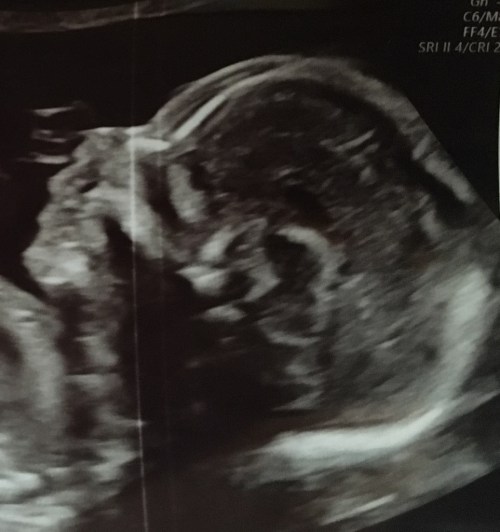

GRAMMY NOTES: We just learned that our newest grand is a little boy. Marine Mama says his brothers have their dada’s chin, but she thinks #3 will look more like our side, cuz that’s a Hyphen chin there. LOL Please keep our daughter and her wee one in your prayers. He is due March 2, but his brothers were both early.